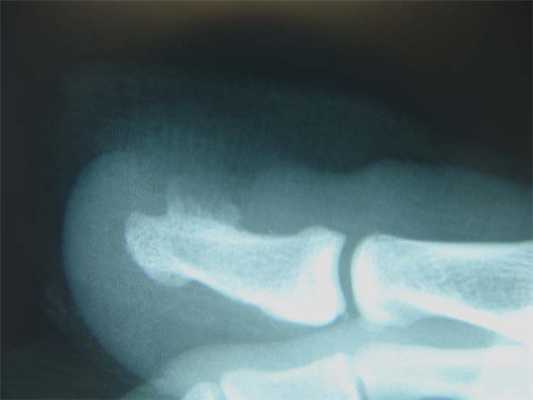

Рентген

Дело в том, что подобным образом могут проявляться и другие заболевания, в частности доброкачественные и злокачественные опухоли. Поэтому для точного установления природы сформировавшегося выпячивания назначаются инструментальные методы диагностики. Как правило, используется рентген. Этот метод дает информацию о состоянии костных структур и будет информативен при длительном существовании подногтевого экзостоза, когда он уже успеет окостенеть. Если же провести исследование, когда выпячивание только появилось, оно может быть безрезультатным, так как на снимках не будет видно хрящевую структуру.

Другие методы инструментальной диагностики используются редко. В основном они требуются в спорных случаях, когда рентгеновские снимки оказались неинформативными. В таких ситуациях пациентам может назначаться МРТ, КТ.